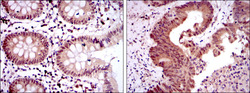

STJ98293 IHC

Immunohistochemistry